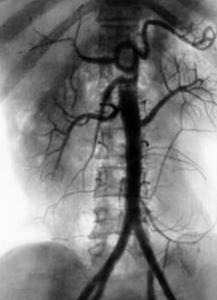

Аортография — это методика рентгенологического исследования аорты, основанная на получении комплексного изображения аорты вследствие заполнения её контрастным веществом. Главным инструментом в данном случае выступает радиоактивное излучение, с помощью которого производятся снимки наполненных рентгенконтрастной жидкостью сосудов.

- Брюшная аортография. Используется для получения дополнительной диагностической информации при заболеваниях почек, кишечника, печени, селезёнки, мочевого пузыря и матки.

При сохранении пульсации артерии в бедренной части прокол осуществляется именно там (методика Сельдингера). В полученный прокол вставляется тонкий струнообразный проводник, посредством которого в дальнейшем вводится катетер. Проводник извлекается, а катетер проводится непосредственно в аорту. После этого производится введение рентгенконтрастного препарата. Далее с помощью рентгеновского аппарата выполняется ряд снимков исследуемой области, после чего катетер удаляется, а на место прокола накладывают асептическую давящую повязку для предотвращения кровотечения. Полученные снимки хранятся на жёстком диске компьютера, что позволяет врачу обращаться к ним в любой момент.